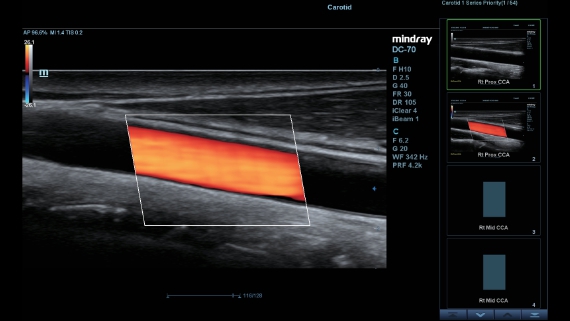

X-Insight ??? ??? ??? ??? ?? ??? ?? ?? ??????.

?????? ??? ???? ?? ???? ??? ??? ??? ???? ??? ??? ??? ?? ??? ???? ?????. ??? ?? ????? ???? ???? ??? ?? ??? ???? ?? ???? ??? ???? ???? ????.

???? ?? ??? ?????, X-Insight???? ??? DC-60 Exp ?? ??? ???? ???? ?? ??? ?? ??? ?? ???? ?????.

X-Insight??? ??? DC-60 Exp? ??? ??? ?? ?? ???? ???? ???(eXpress) ???, ???(eExceptional) ?????, ???? (eXceeding) ?? ??? ?? ????, ??? ???? ??? ??? ?? ???? ?????.